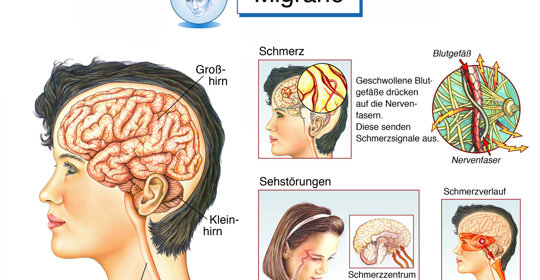

搏動性頭痛:腦海的地雷,症狀揭秘與緩解方法

劇烈頭痛:頭部的急救信號,症狀及科學調理方法詳解